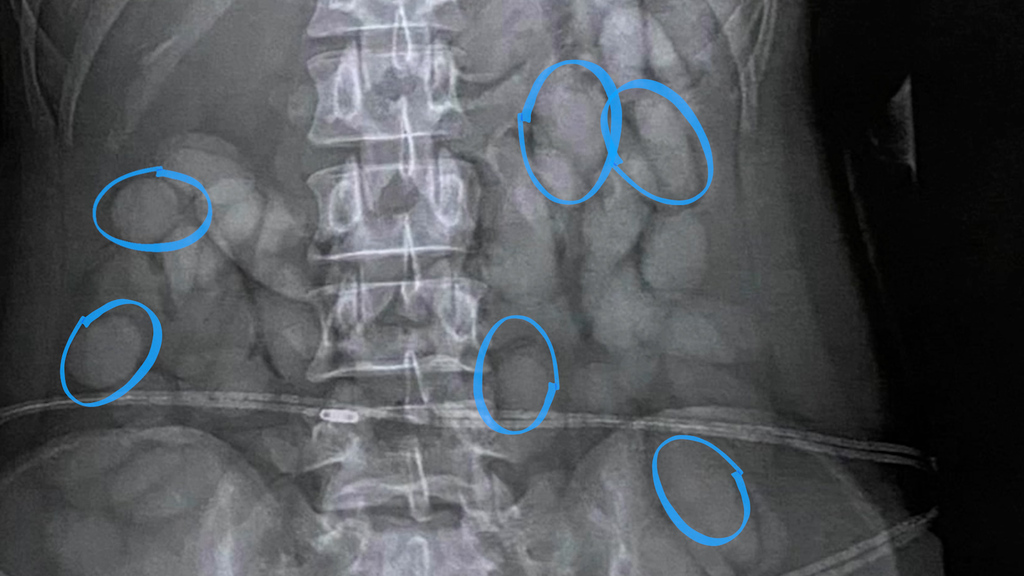

Drogenschmuggel aufgeflogen: Verdächtige mit 63 Kugeln Kokain im Magen abgefangen

Eine Passagierin wurde nach einem Hinweis auf Drogenschmuggel an einem südafrikanischen Flughafen verhaftet. Ein Röntgenbild zeigt: Die junge Frau trägt eine grosse Menge an Kokain in ihrem Körper.